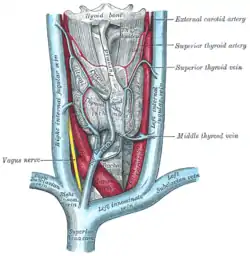

The thyroid gland and its relations. (Middle thyroid vein labeled at center right.) | |